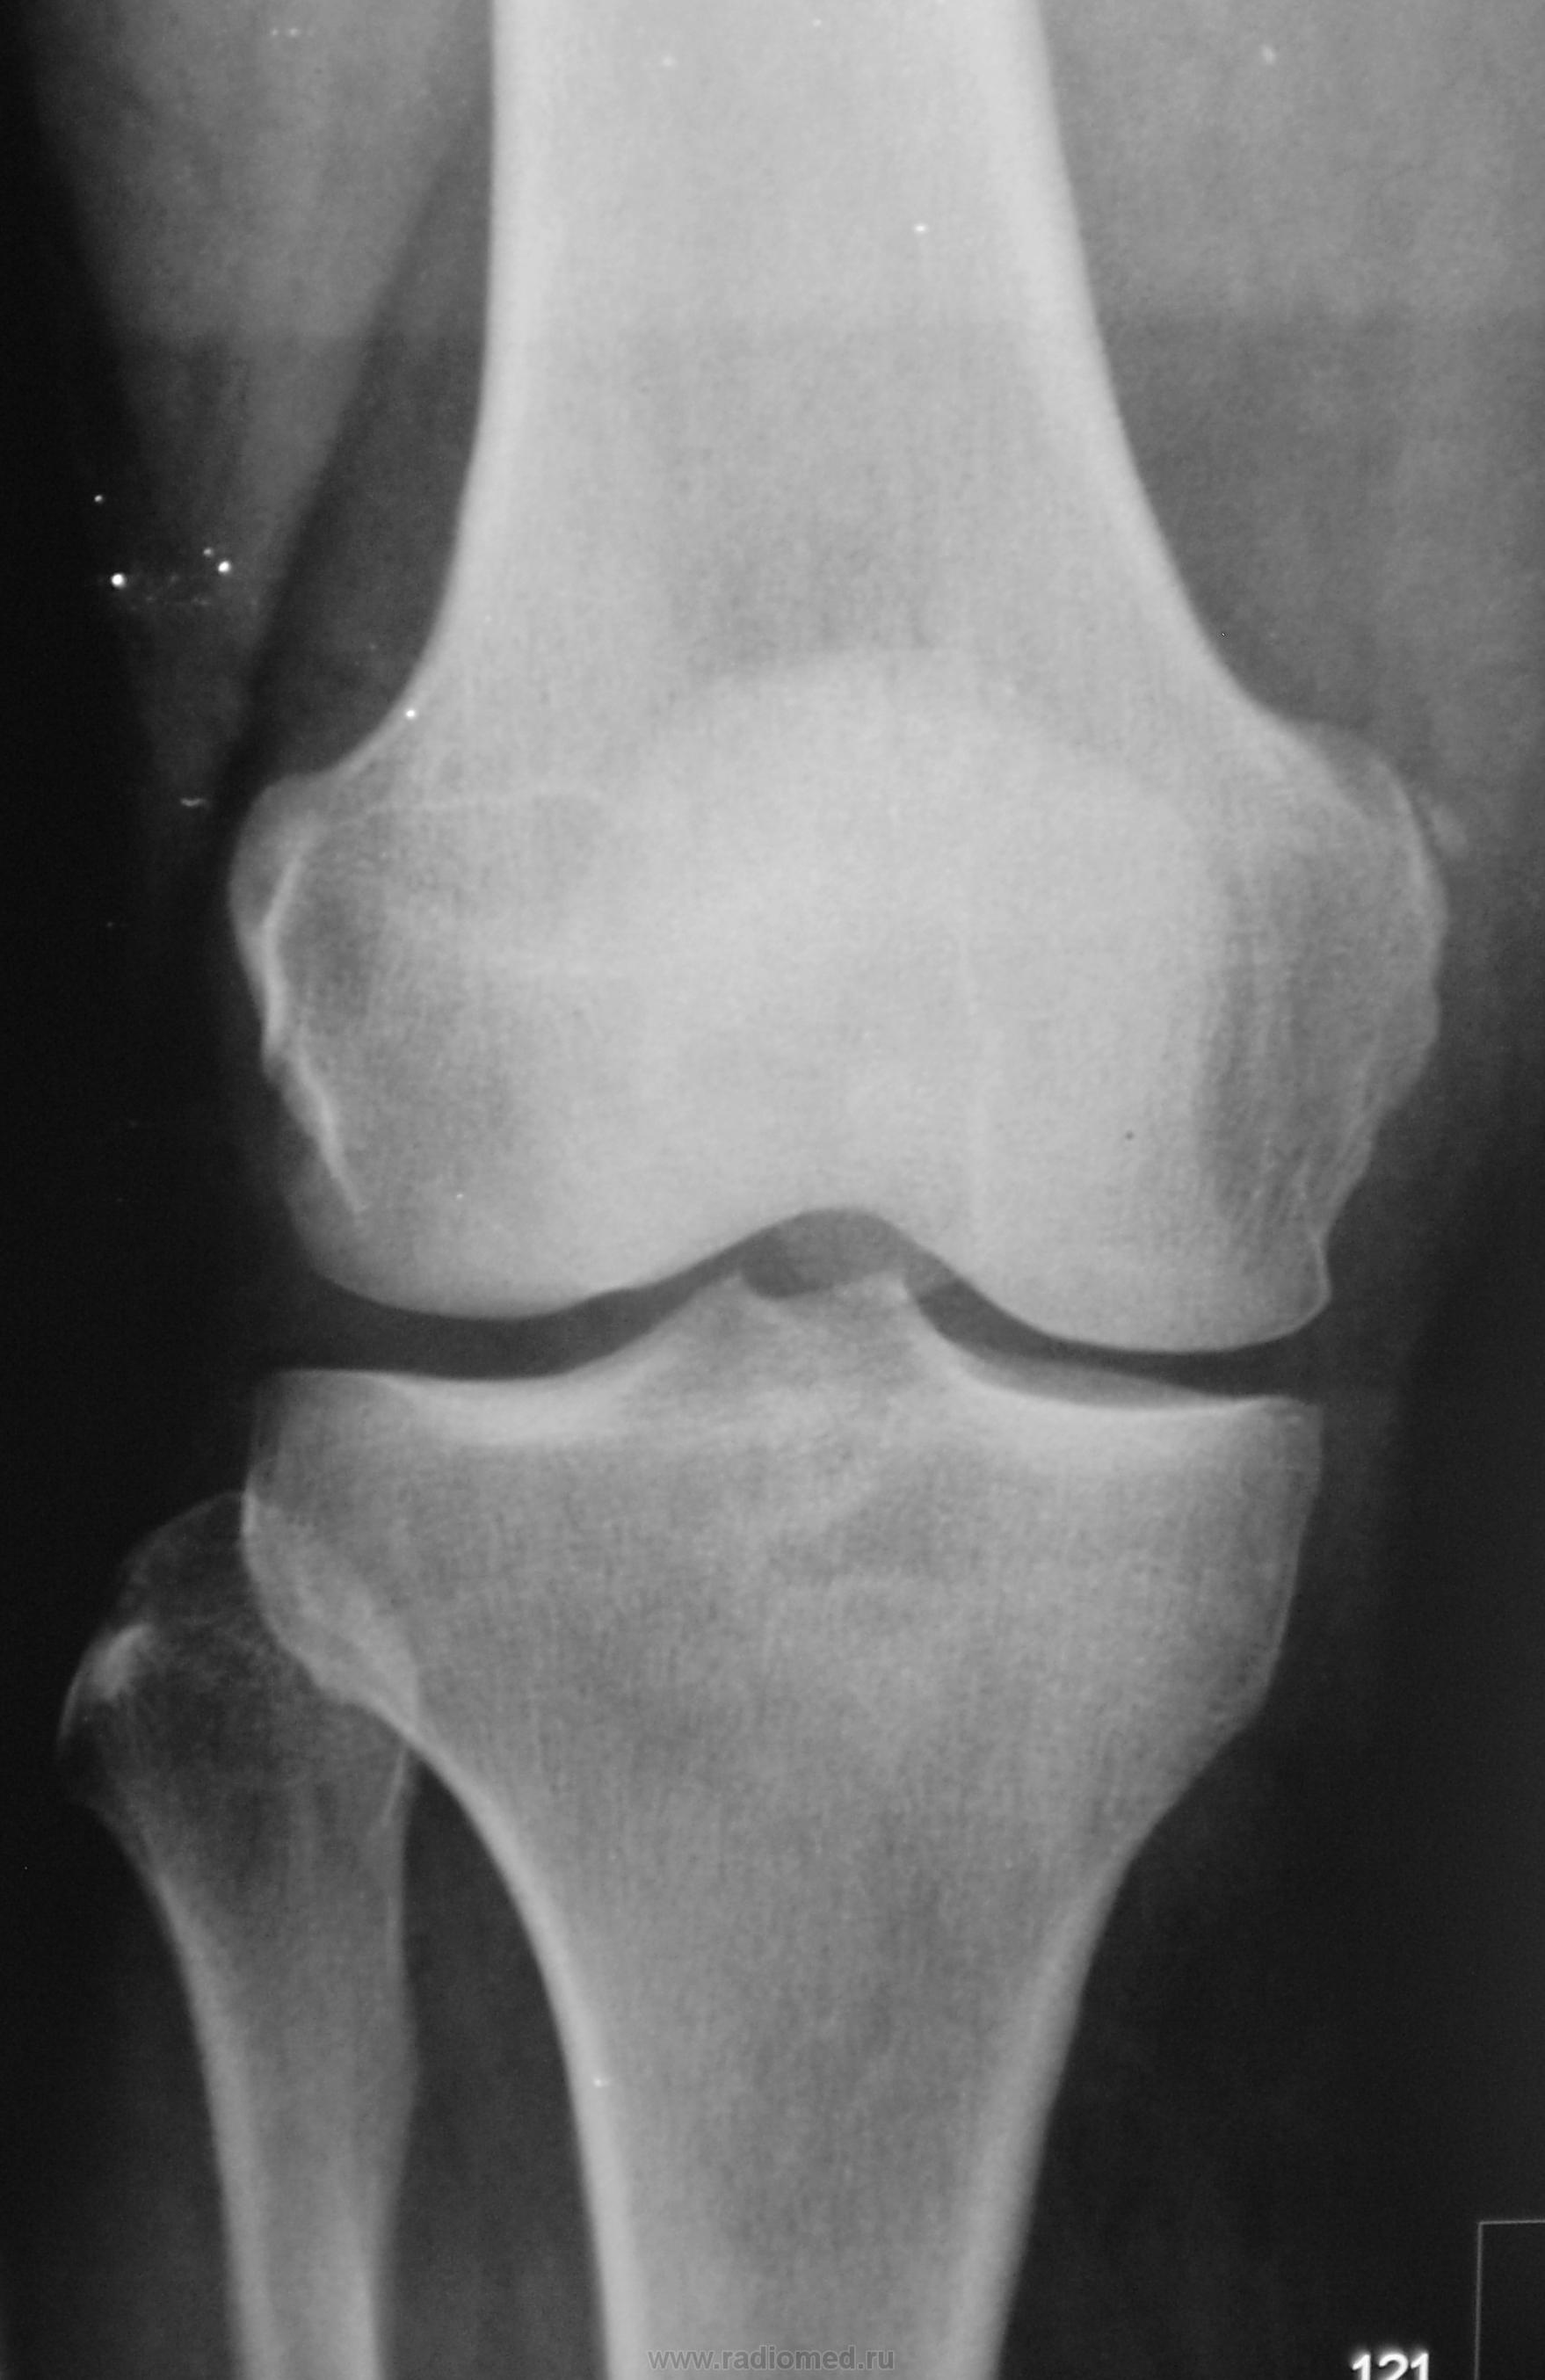

Травма. Пациент направлен на рентгенографию коленного сустава.

Данная картина больше напоминает болезнь Пеллегрини-Штида, обызвествления сухожилия мышцы.

Пеллегрини-Штида

Участок обызвествления у медиального надмыщелка бедренной кости. Возможно оскольчатый перелом.

Костно-травматических изменний не выявлено. Участок линейного обызвествления у медиального надмыщелка бедренной кости - болезнь П.-Ш. (это я сократилаsmiley)

Вот , был ещё один случай.